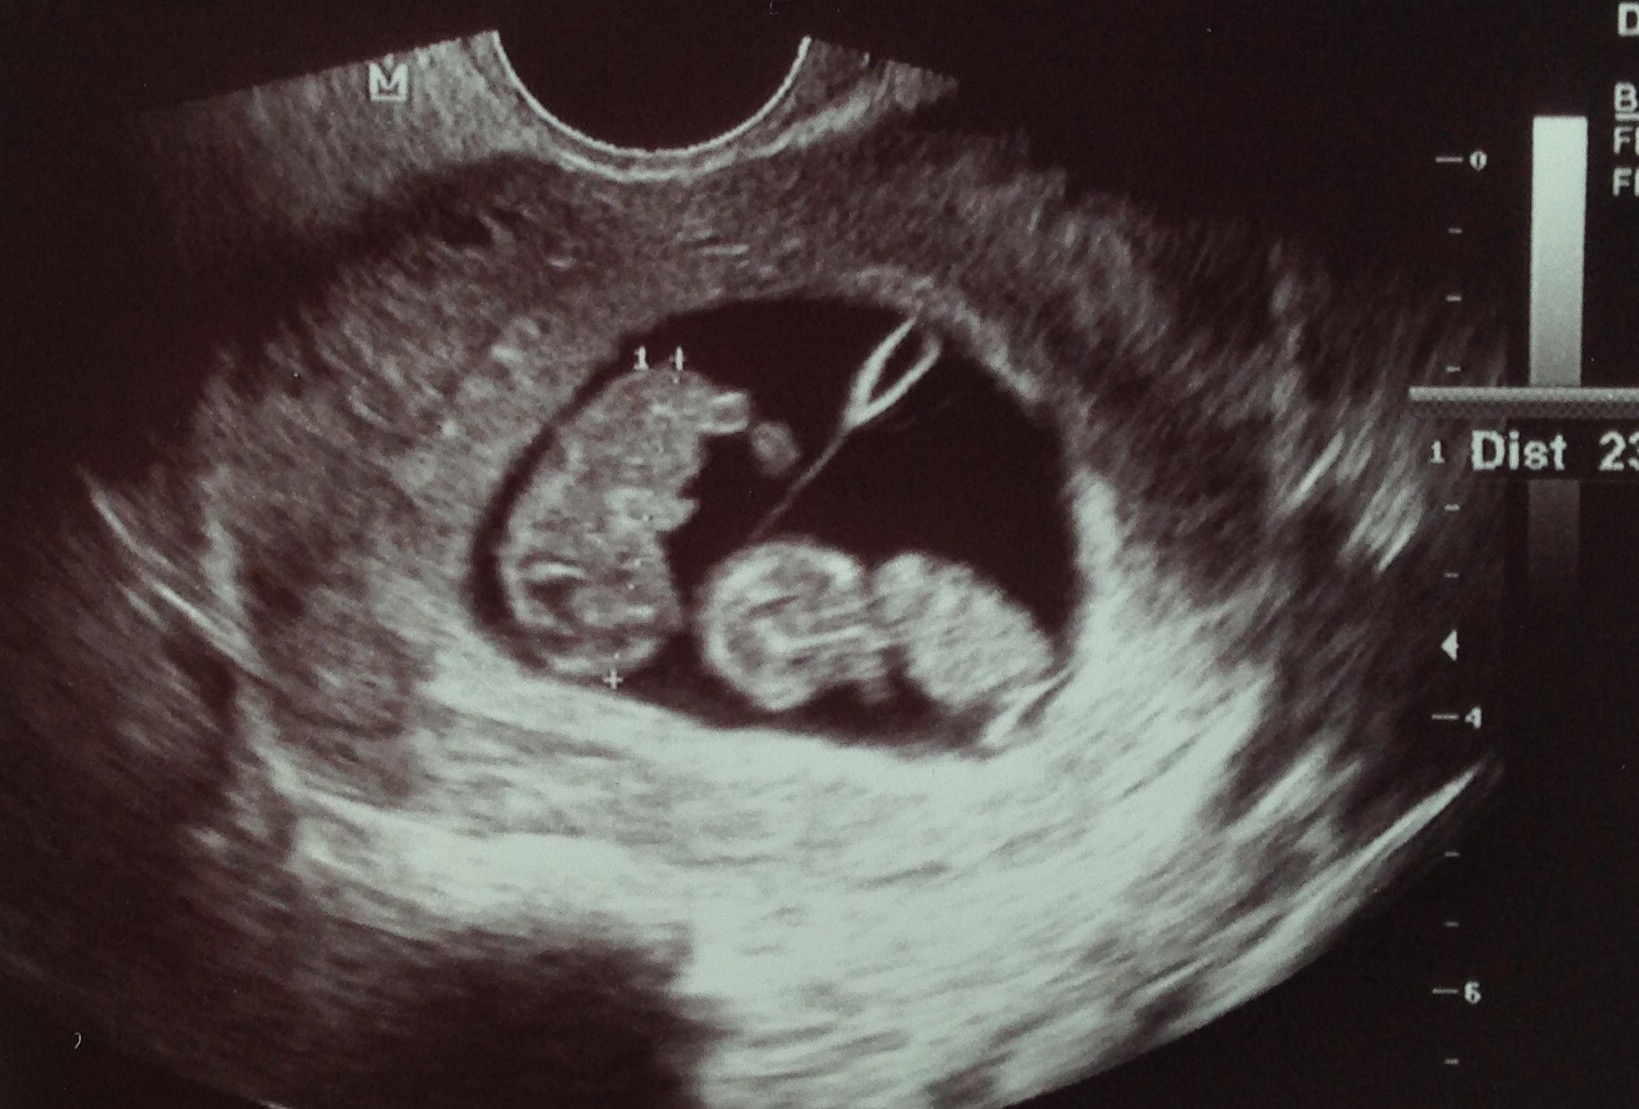

This isn't our first ultrasound, it's actually our 3rd! Our first was 5w5d (and saw a developing HB), then we had one at 6w5d and today was 8w! We will have one every week until I'm out of my first tri (3 previous losses and I have an incredible OB who is looking to keep my anxiety at bay!)